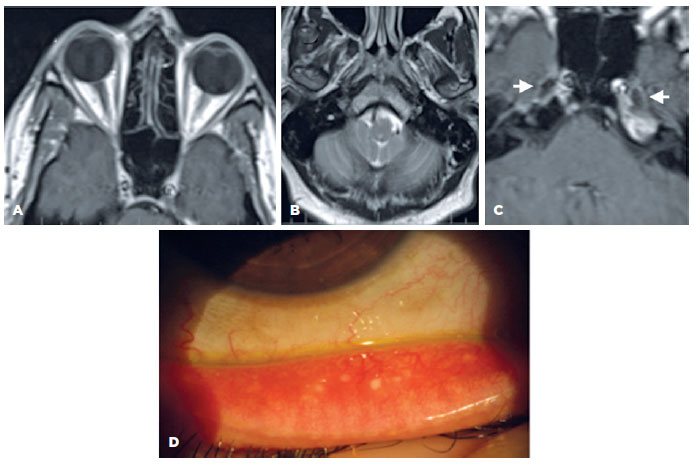

A 24-year-old white woman presented with DES over the last three years without dry mouth. She reported no comorbidities and no use of medications, except for treatment of acne with RA at 14 and 20 years of age, lasting for six months on both occasions. The ophthalmological examination demonstrated a visual acuity of 1.0 in both eyes (OU); a tear film break-up time (TFBUT) of 2 s in the right eye (OD) and 1 sin the left eye (OS); a grade 5 corneal fluorescein staining in OD and grade 3 in OS, with filamentary keratitis; and a Schirmer test (ST) showed absent tear flow (zero mm) in OU. Moderate MG dysfunction (MGD) with less than 30% of gland drop out, light expressibility, and cloudy oil secretion were observed. The ocular surface disease index (OSDI) was 70.45%, and the whole saliva flow was 0.13 ml/min (normal value, >0.1 ml/min). Serological tests for autoimmune and viral systemic diseases, including anti-Ro/SSA, anti-La/SSB, anti-dsDNA, anti-SM, anti-RNP, antinuclear antibody (ANA), and rheumatoid factor, were negative. A biopsy of her minor lip SG revealed a focus score of zero. MRI revealed the absence of the LG bilaterally (Figure 1A). The average normal LG volume is 0,580 cm3.

11-fig01tb.jpg)